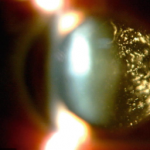

Ocular melanoma is a rare form of cancer that occurs in the pigment producing cells of your eyes. Ocular melanomas usually develop in the middle of the three layers of your eye, called the uvea. In rare cases, the melanoma can also develop on the conjunctiva.

- Dark spot on the iris or conjunctiva

- Change in pupil shape

Melanomas are distinctly different from moles— melanomas are more orange, thicker, and leak fluid. Your eye doctor will look for signs of melanoma through specialized diagnostic tests and equipment.